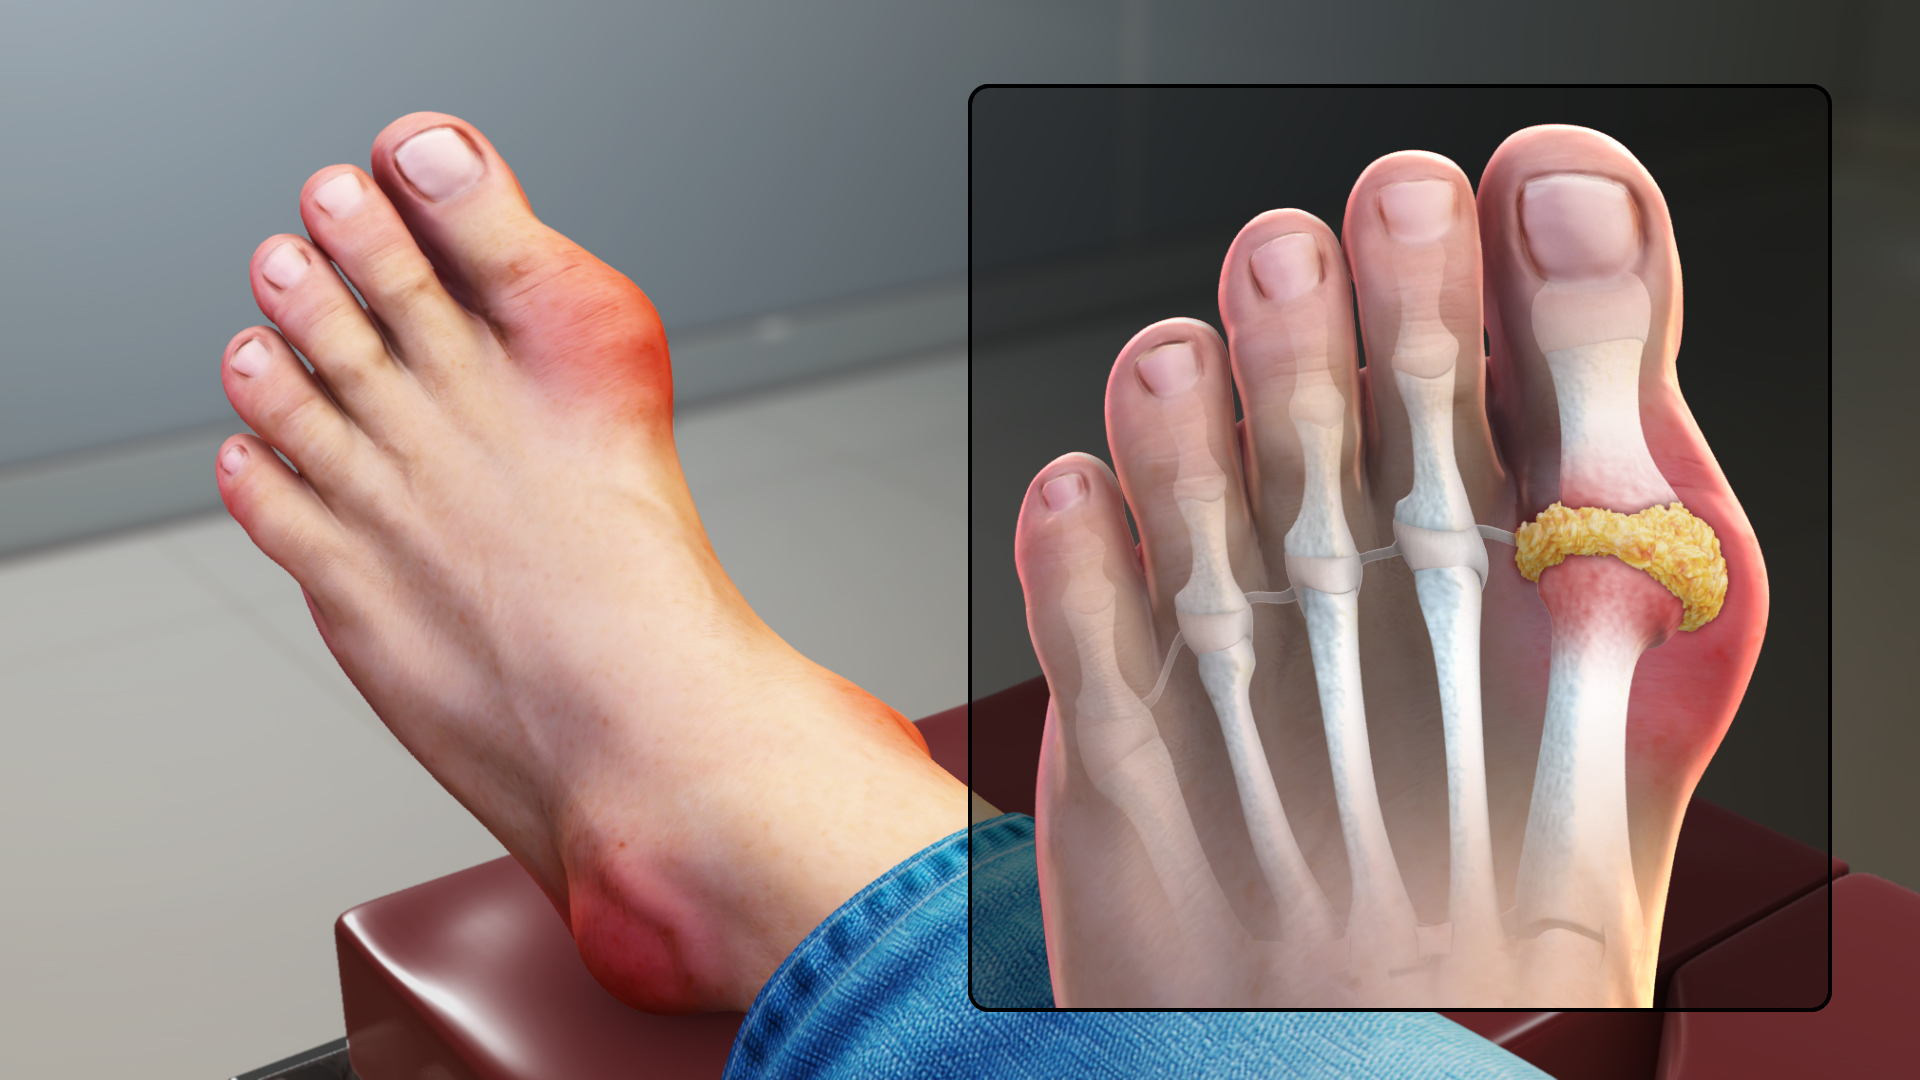

통풍

요산 결정이 관절에 쌓이면서 염증을 유발하는 질환입니다. 주로 엄지발가락 관절에 통증이 시작되지만, 발바닥 전체로 통증이 확산되기도 합니다. 심한 경우 붓기와 열감이 동반되어 신발 착용이 힘들 정도가 됩니다.